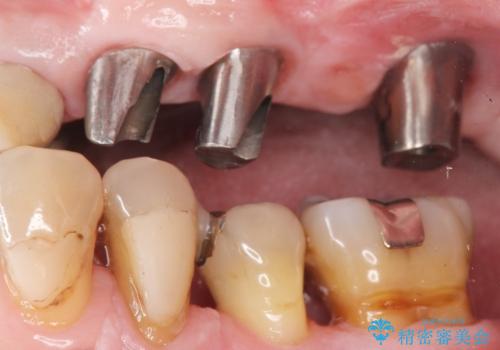

- 歯がぐらぐらで咬めないことを主訴に来院された患者様です。

他院では上顎骨が薄いためインプラントできないと言われたとのことでした。

精査したところ、歯周病に罹患した歯を長年放置したことから骨吸収が進行し、上顎骨の厚みはとても薄くなっていました。

全顎的な歯周病治療を行ったのち、上顎洞底挙上術(上顎骨に骨を増やす手術)を併用したインプラント埋入を行いました。